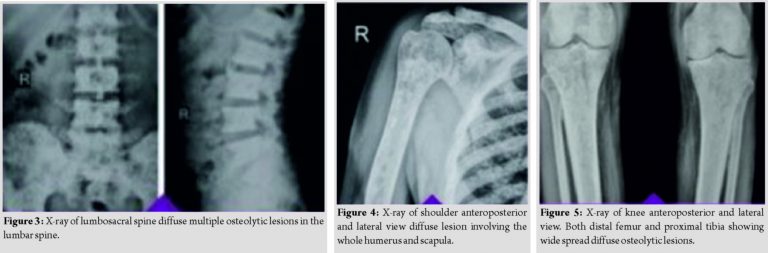

The patient then visited our tertiary center where the thorough skeletal survey was done, which showed involvement of pelvis (Fig. 1 and 2), spine (Fig. 3), and appendicular skeleton(Fig. 4 and 5) as well. The lesions were osteolytic, small, multiple, of varied sizes involving the whole of the involved bone, rather symmetrically (Fig. 6).

The X-ray with which the patient presented showed superior cortical breach in the femoral neck, but on traction X-ray, the pathological trans-cervical neck femur fracture was noted (Fig. 1). Differential diagnoses considered were metastasis, osteopoikilosis, and multiple myeloma.